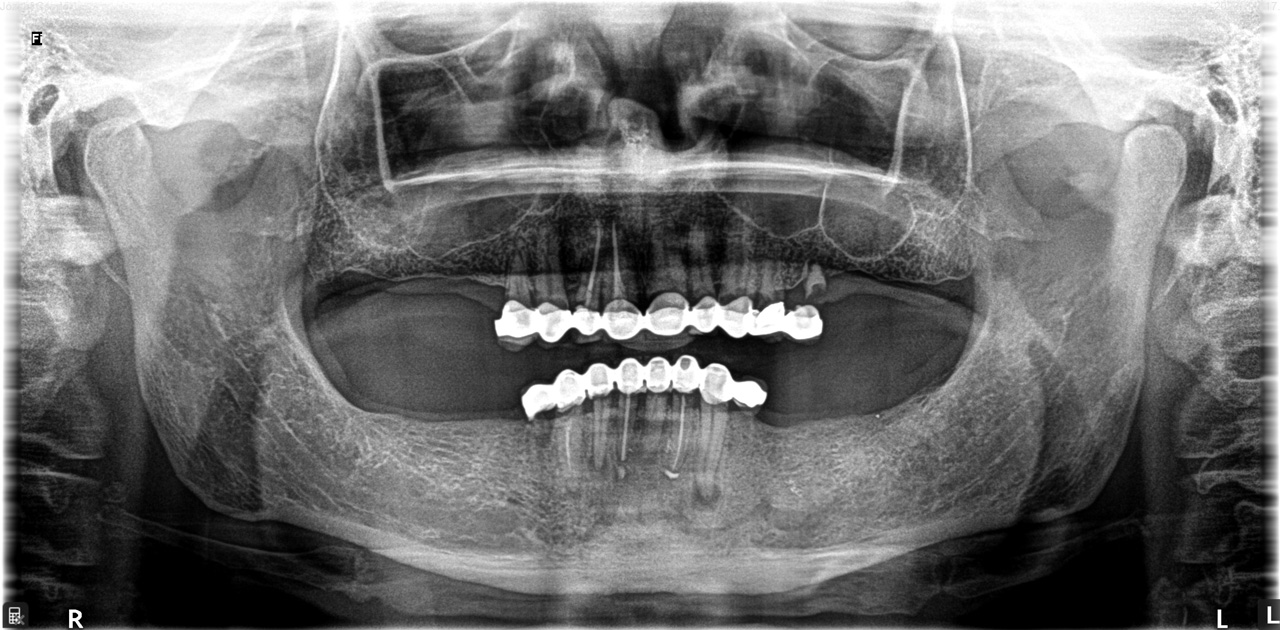

Alsó állcsont teljes rehabilitációja 72 óra alatt, azonnal terhelhető implantátumokkal súlyos paradontitisben szenvedő dohányzó páciens esetében. Az alsó állcsont fogai mind mozogtak az előrehaladott fogágypusztulás miatt.

A fogakat eltávolítottuk, a gyulladt, fertőzött csontot kitakarítottuk, kifertőtlenítettük, majd azonnal implantáltunk.

Svájci, IHDE márkájú, azonnal terhelhető implantátumokat helyzetünk be, és ezekre harmadnapra rögzített, hosszútávú, fémvázas, esztétikus műanyaggal leplezett hidat ragasztottunk be.

Ezt az ideiglenes hidat a sebek gyógyulása miatt használjuk, de tartóssága miatt véglegesként is használható. A legtöbb esetben, ahogy itt is, 6 hónap múlva porcelán hídra cseréljük, a teljes gyógyulás után.